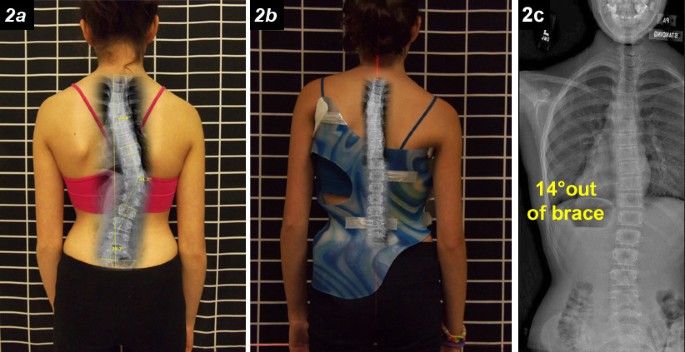

علاج الجنف لا يقتصر على الحزام PioBrace أو الجراحة فقط. فهو يحتاج إلى تدريب الدماغ والجسم على التوازن الصحيح أيضًا.

الفحص بسيط وغير مؤلم، ويمكن أن يكتشف الخلل في حركة الرقبة مبكرًا قبل أن يؤثر على تطور الانحناء.

التدخل المبكر والعلاج المنتظم يساعدان على تحسين التوازن ومنع زيادة الاعوجاج أثناء النمو.

الاعوجاج حالة مستمرة ولهذا السب قد تحتاج تدخلًا في مراحل مختلفة من العمر. وبفضل وجود تقنيات التصنيف المعتمدة ، يمكن للأطباء تصميم خطة علاجية مخصصة تضمن تدخلاً جراحيًا عند الضرورة أو العلاج غير الجراحي قبل ذلك، لتفادي الاضطراب في الوظائف التنفسية أو أي أعراض متأخرة. فريقنا المحترف يضم نخبة من الأطباء والمتخصصين الذين يجمعون بين الخبرة والاحترافية لتقديم خطة علاجية غيرر جراحيه شاملة ومخصصة لحالتك، تضمن السيطرة على الانحناء ومنع زيادته.

خطط علاجية مخصصة: نوفر برامج علاجية مصممة خصيصًا لكل حالة لضمان أفضل النتائج دون الحاجة للجراحة.

أحدث التقنيات العالمية: نعتمد على تقنيات حديثة مثل أجهزة التقييم الدقيقة وأحزمة التقويم المتقدمة مثل PioBrace.